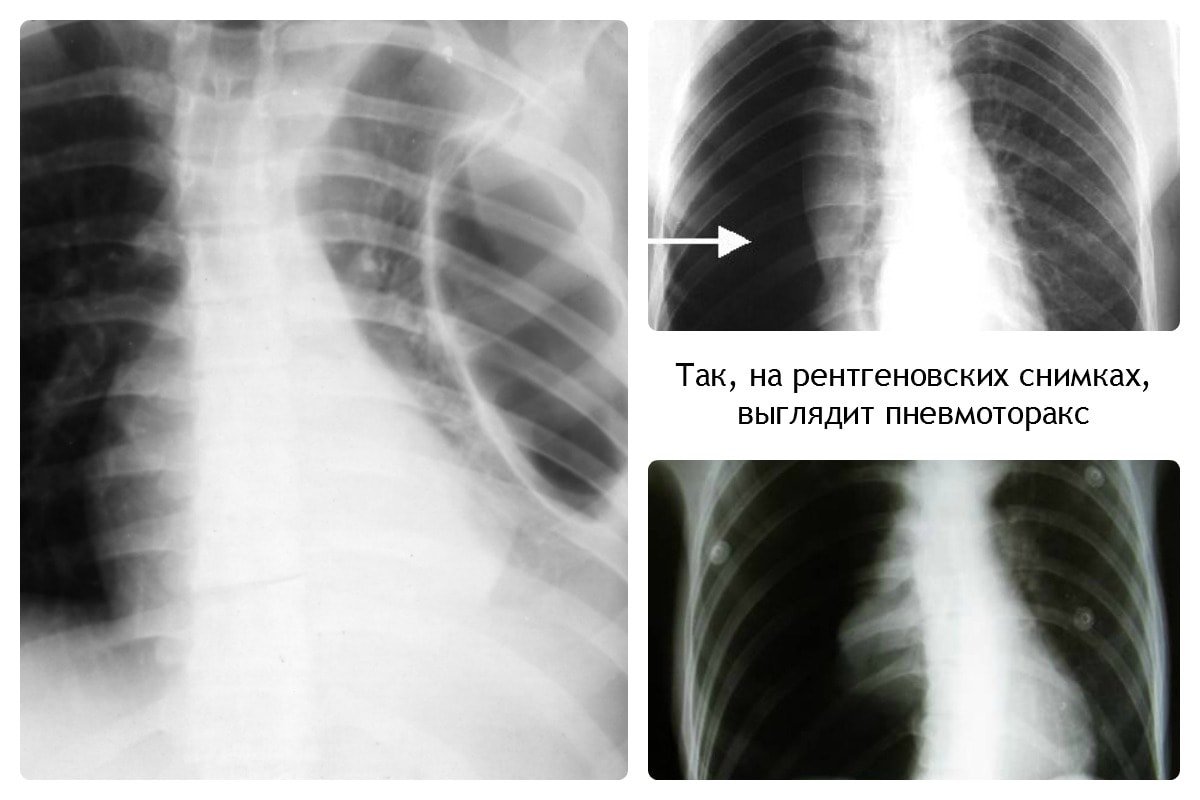

При пневмотораксе присутствует характерный уровень жидкости. На снимке отображается как просветление, лёгочный рисунок не просматривается.